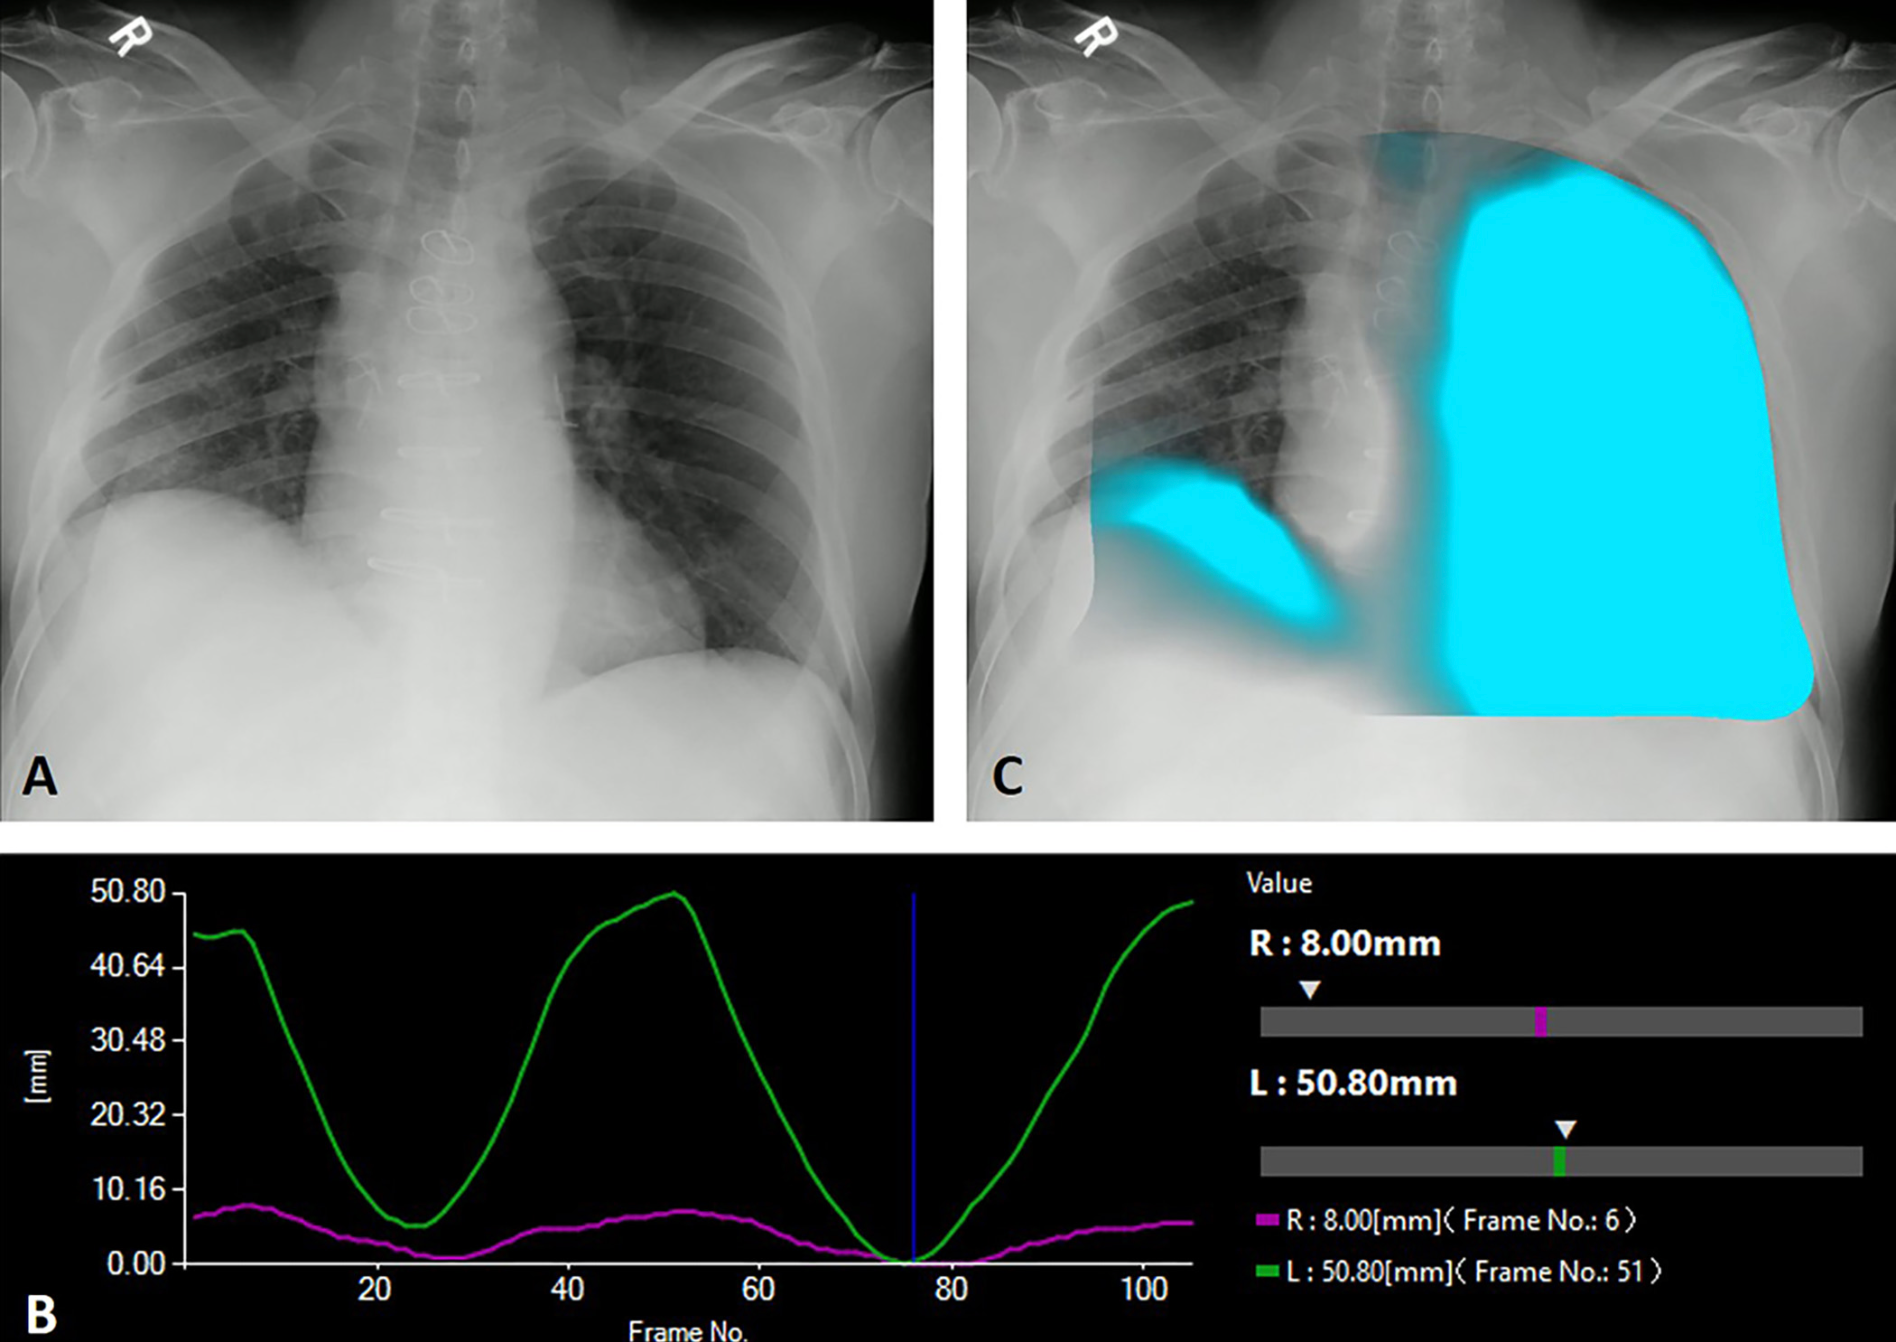

Portable Dynamic Digital Radiography Detects Airflow Impairment Following Lung Transplantation